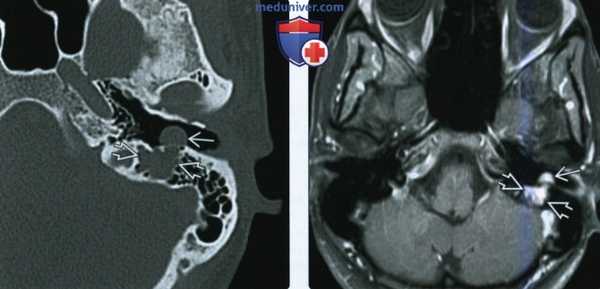

(Слева) МРТ Т1ВИ FS с КУ, аксиальная проекция. У переднего края поверхностной доли правой околоушной железы определяется округлое образование 0. Имеются участки неоднородного накопления контраста с включениями кист. Обратите внимание, что закупорка выводного протока опухолью привела к развитию паротита.

(Справа) МРТ Т2ВИ FS, аксиальная проекция. Визуализируется округлое образование с неоднородным сигналом высокой интенсивности, которое расположено в области переднего края поверхностной доли околоушной железы. Отличить такое образование от доброкачественной смешанной опухоли, которая встречается гораздо чаще, практически невозможно. (Слева) КТ с КУ, аксиальная проекция, выполненная у пациента с нейрофиброматозом 2 типа. В области переднего края поверхностной доли околоушной железы имеется округлое образование размером менее 1 см. Шваннома неравномерно накапливает контраст, но из-за небольших размеров участки кистозного перерождения отсутствуют.

(Слева) На аксиальной МРТ (Т1 ВИ С+ FS) в передних отделах поверхностной доли околоушной железы визуализируется округлое объемное образованней Опухоль неравномерно накапливает контраст, видны разбросанные кистозные участки. Обратите внимание на паротит обусловленный обструкцией протока шванномой.

(Справа) На аксиальной MPT (Т2 ВИ FS) в передних отделах поверхностной доли околоушной железы визуализируется опухоль округлой формы с неоднородным гиперинтенсивным сигналом. Такое новообразование сложно отличить от значительно более частой доброкачественной смешанной опухоли.

(Справа) МРТ Т2ВИ FS, аксиальная проекция. Визуализируется округлое образование с неоднородным сигналом высокой интенсивности, которое расположено в области переднего края поверхностной доли околоушной железы. Отличить такое образование от доброкачественной смешанной опухоли, которая встречается гораздо чаще, практически невозможно.